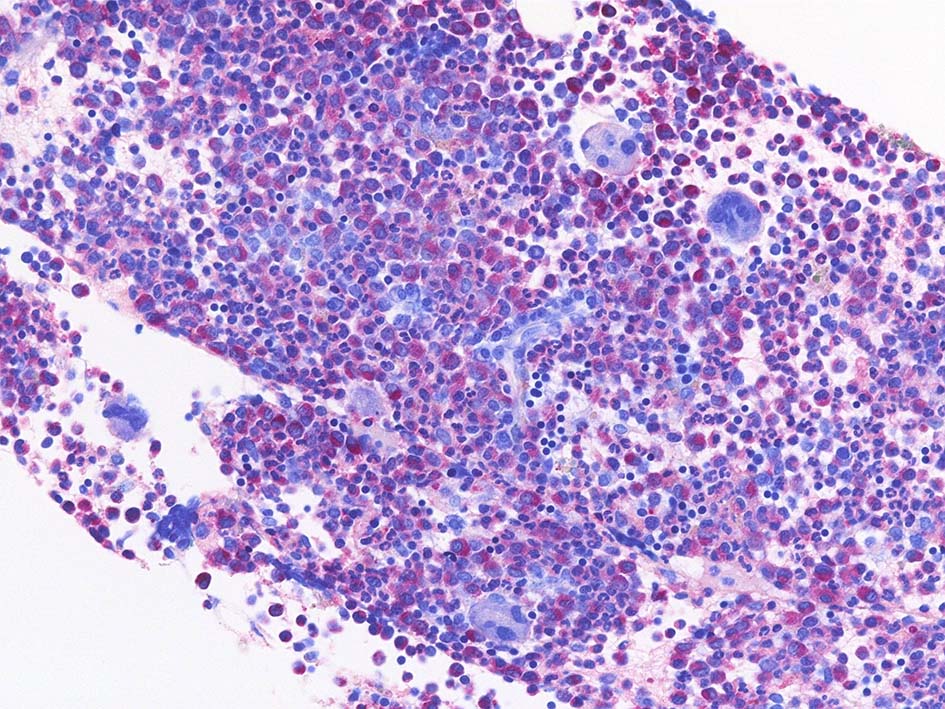

Fig.01: hypercellular marrow. ASDで赤染する細胞の増加=granulopoietic hyperplasiaがある.

Fig.02: 幼若な顆粒球が増加している. 赤芽球は散在しており血島は不明瞭である. 過形成髄なのにFig.02に成熟大型巨核球はみられない.